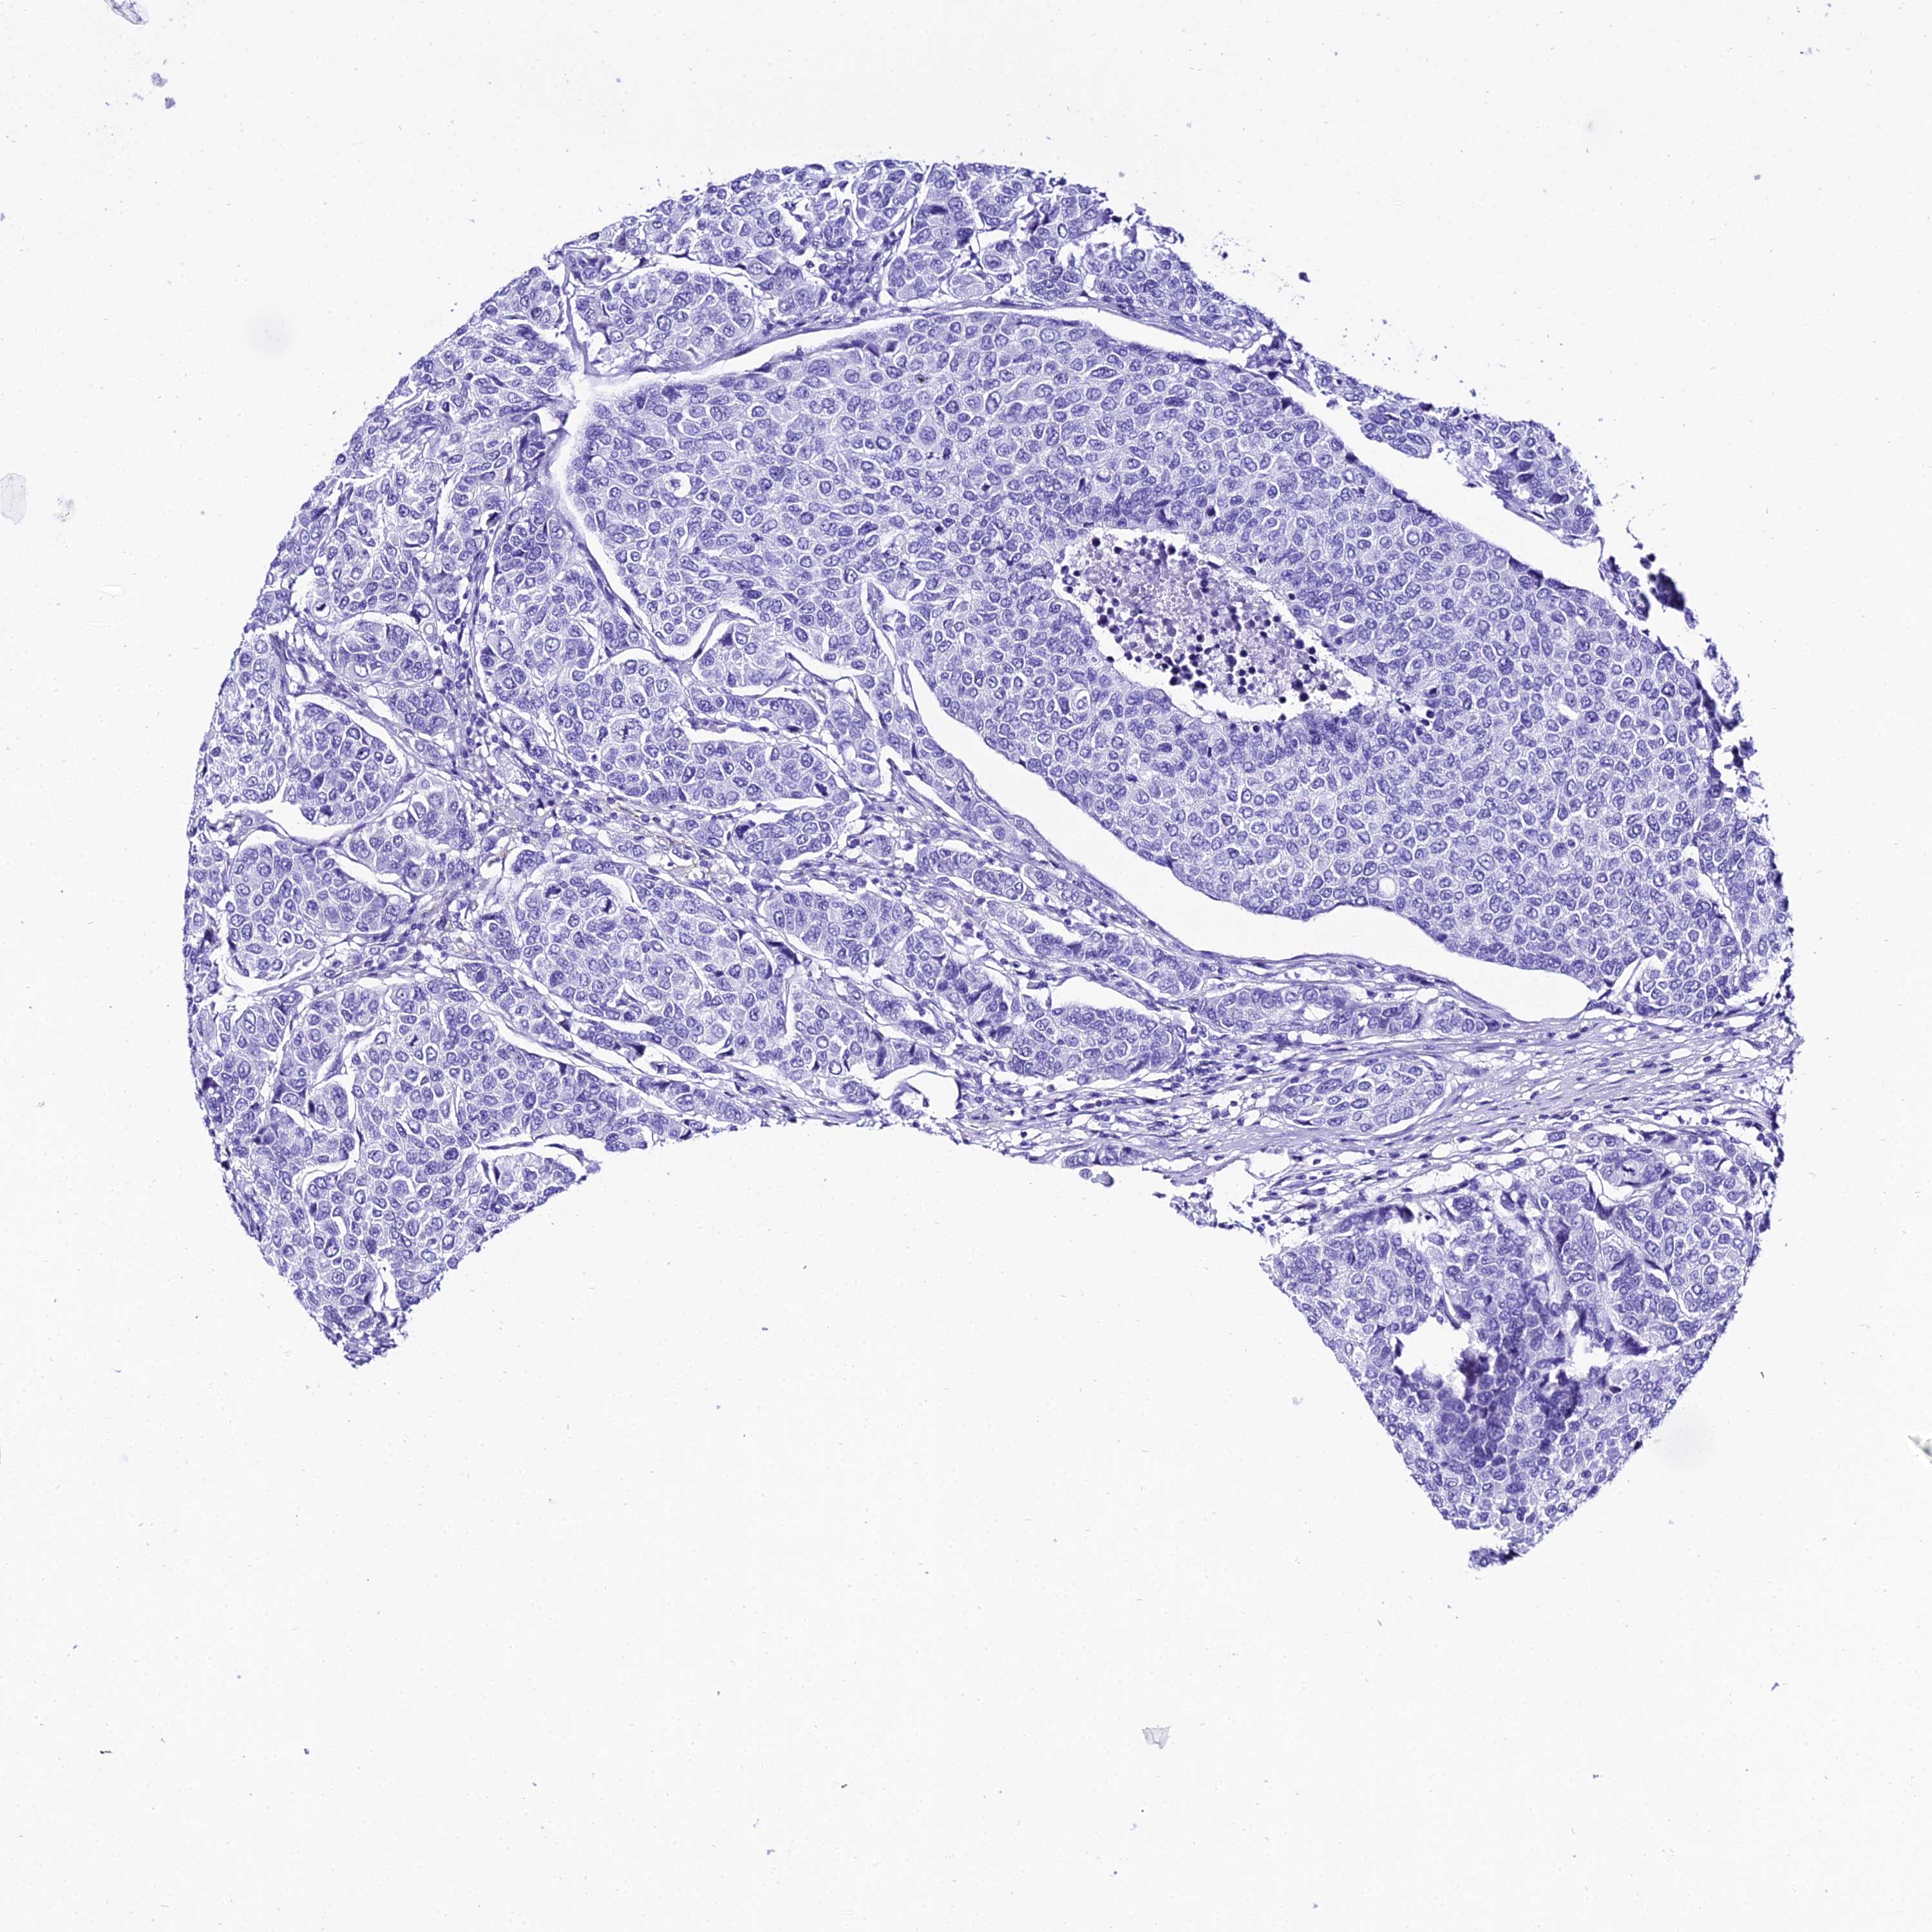

CANCER BREAST CANCER Show tissue menu

Breast cancer

Human cancer